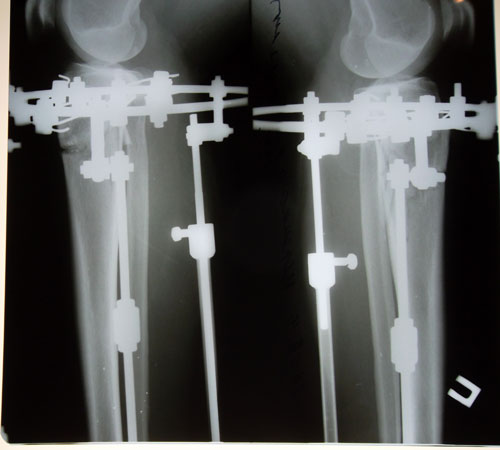

Рентген на 23 день после операции. Сращение идёт хорошо!

Вложения

SAM_9887.JPG

SAM_9889.JPG